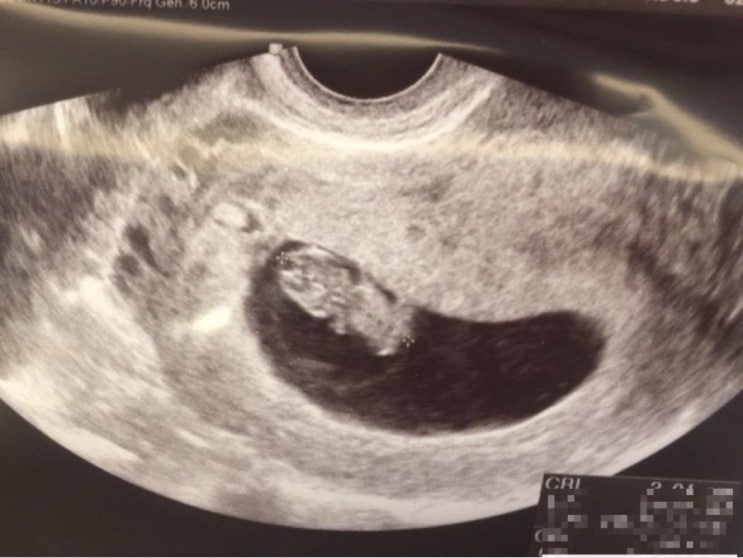

[블로그 포토덤프 챌린지] 40주 5일 임신기간 기록

이번 스페셜 포토덤프 챌린지는 임신! 테스트기 확인 후 산부인과를 방문하여 애기집을 눈으로 확인하고말...